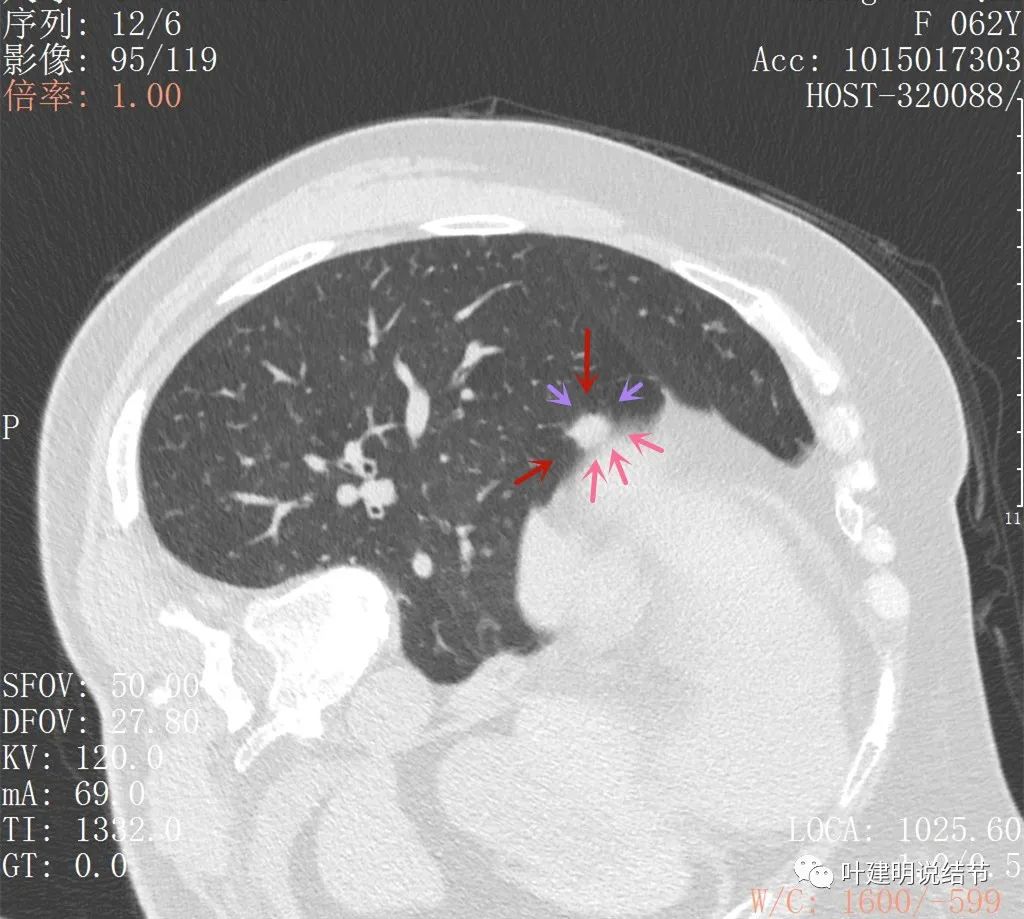

这是最近一次平扫的片子,此结节感觉有膨胀感,边界较清,位于肺底,贴膈面。我们从数次复查的对比,看来该结节是缓慢进展的,不吸收也不钙化,也不是纤维增生或条索状瘢痕的样子。在门诊我仔细对比了这些不同时间的片子后,认为右下这结节也极可能是恶性的,该干预。所以我们进一步查了靶扫描:

病灶出现,与膈肌间隙欠清

病灶呈实性密度,与膈肌间在此层面上看,并不侵犯或粘连,还是有缝隙的

上图粉色箭头示与膈肌间的缝隙,紫色箭头示病灶有细毛刺征,红色箭头示病灶实性密度